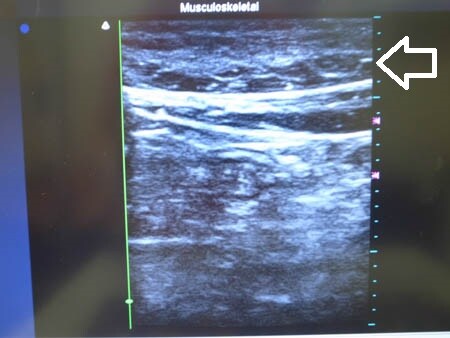

今回は3Dタッチビュー(=超音波)

を用いて皮下脂肪層の状態を

適宜チェックしながらの手術になりました。

上腹部の皮下脂肪の状態を

手術直前と直後で比較して見てみましょう。

↓ ↓ ↓